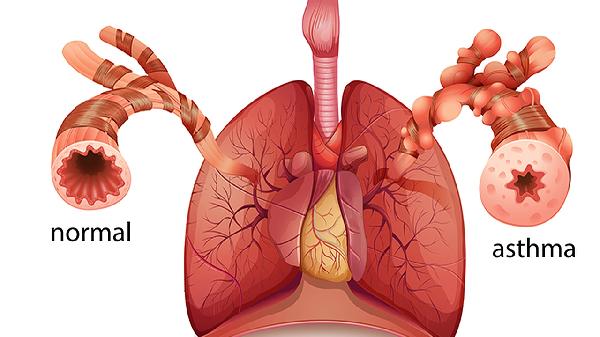

CT引導(dǎo)下肺穿刺活檢主要用于肺部結(jié)節(jié)、腫塊等病變的性質(zhì)鑒別。操作時(shí)患者需保持固定體位,醫(yī)生在CT掃描引導(dǎo)下確定穿刺點(diǎn),局部麻醉后經(jīng)皮膚插入細(xì)針至目標(biāo)病灶,抽取少量組織樣本。該技術(shù)具有定位精準(zhǔn)、創(chuàng)傷小的特點(diǎn),可明確肺癌、肺結(jié)核、肺炎性假瘤等疾病的病理診斷。